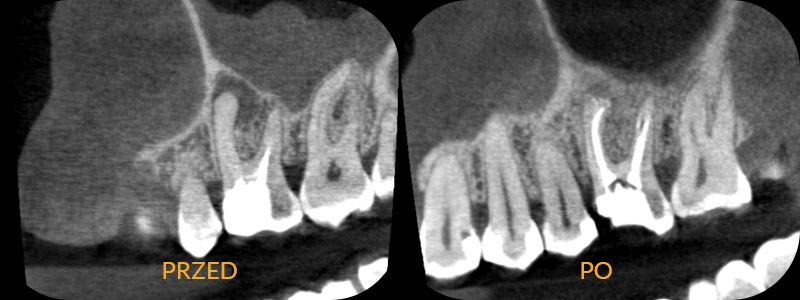

Wielu pacjentów, mających kłopot z zatokami nie wie, że źródłem mogą być zęby! Nieprawidłowe leczenie kanałowe u pacjentki stało się ogniskiem bakterii powodującym infekcję zatoki. Na zdjęciu widoczne nieprawidłowe leczenie kanałowe - kanały niedopełnione, pominięty w pierwotnym leczeniu 4 kanał. Zmiana zapalna okolicy korzenia i pogrubiona zapalnie błona śluzowa zatoki szczękowej. Przeprowadzono prawidłowe leczenie kanałowe. Po trzech miesiącach badanie kontrolne cbct wykazuje wygojenie kości i zatoki.